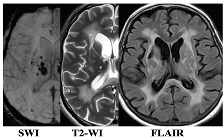

2.1. Clinical and Neuroimaging Characteristics of Two MRI Types of CSVD

| F3 MRI Type 1 | F3 MRI Type 2 |

| WMH: more pronounced in the periventricular and deep regions of the cerebral hemispheres, subcortical structures, external capsule, brainstem, and cerebellum | WMH: periventricular—in the posterior cerebral hemispheres, deep—in the frontal and parietal lobes |

| Lacunes: multiple in subcortical structures and cerebral white matter | Lacunes: single in the white matter of the cerebral hemispheres |

| CMB: juxtacortical CMHs in all regions of the cerebral hemispheres, in subcortical structures | CMB: single juxtacortical CMHs in the white matter of the temporal and parietal lobes |

| Cerebral atrophy: more pronounced | Cerebral atrophy: less pronounced |

| Enlarged PVS: pronounced in subcortical structures | Enlarged PVS: extended |